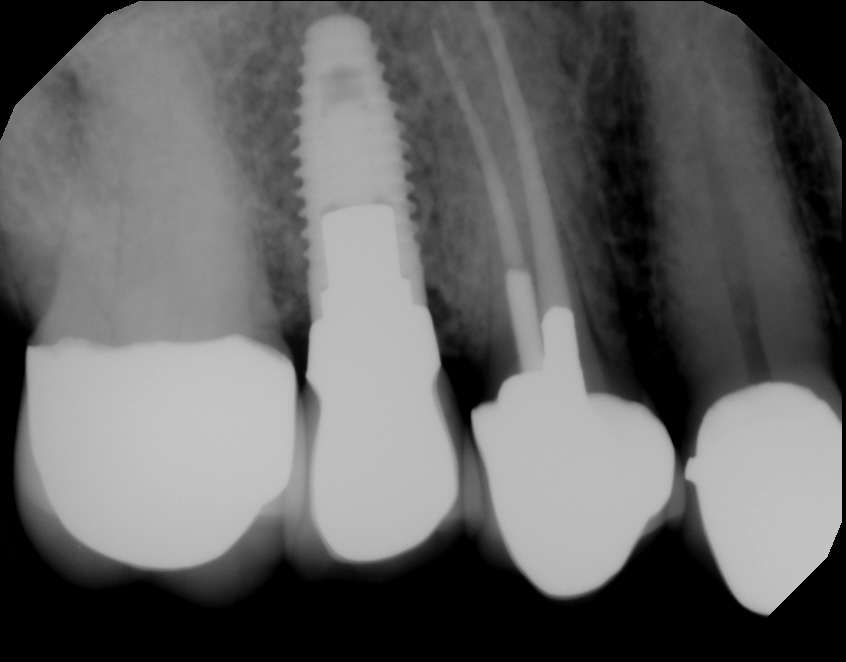

Learn About Single Tooth Dental Implants

If our Rancho Cucamonga Dentist discover you to be a candidate for a dental implant, we will conduct a thorough comprehensive examination and review your medical and dental history. In addition, our Rancho Cucamonga Dentist will then figure out if you have a systemic...

Getting A Better Understanding Of Dental Implants

Dental implants have have innovated the replacement of teeth. Before the development of dental implants, people with dentures were not able to chew a variety of foods; this has been revised with the widespread use of dental implants. According to the Dental Tribune,...

What Are Conventional Dental Implant Options?

In simple terms, dental implants are metal posts or frames that are surgically placed into the jawbone underneath your gums. Once in position, they give your local Rancho Cucamonga Dentist an opportunity to safely mount replacement teeth onto them. How Exactly Do They...

The Different Types Of Implants – Rancho Cucamonga Dentist

Basically, dental implants are metal articles or frames that are surgically placed into the jawbone underneath your own teeth. Once in position, they supply your local Rancho Cucamonga Dentist an opportunity to safely mount replacement teeth on them. Rancho Cucamonga...